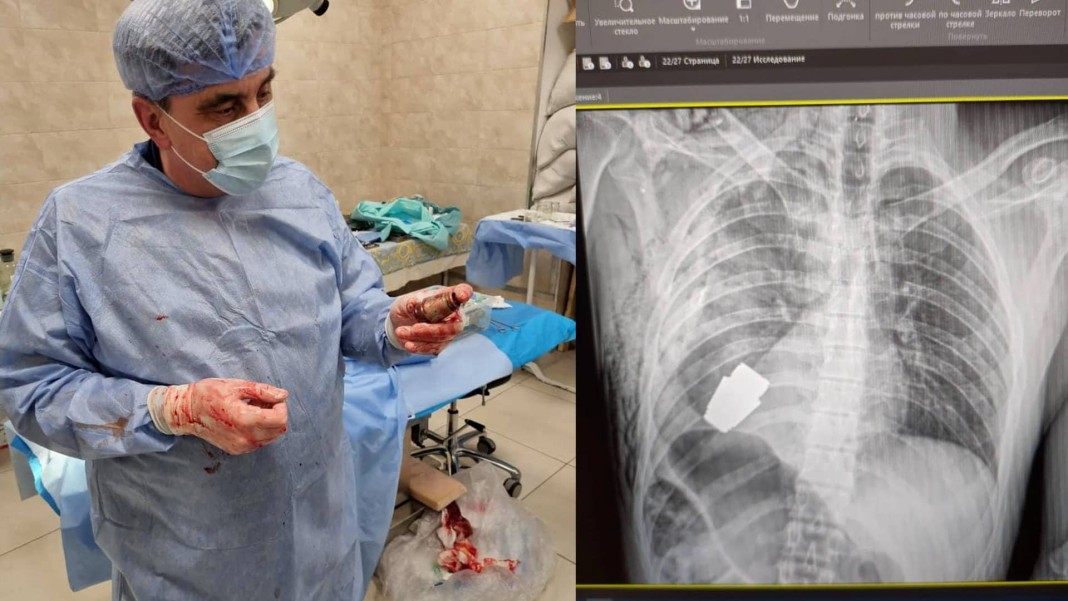

Des médecins militaires ont réalisé une opération unique pour retirer une grenade VOG non explosée du corps d’un soldat.

Comme le révèle le New York Post, un soldat ukrainien a eu la vie sauve après une opération à haut risque. Lors d’une bataille sanglante à Bakhmut en Ukraine, le militaire s’est retrouvé avec une grenade réelle logée… dans son torse. Il a donc dû la faire enlever chirurgicalement, en urgence, au risque d’y laisser sa vie. Seulement voilà : la grenade pouvait exploser à tout moment.

Dans un premier temps, une électrocoagulation a été envisagée. Il s’agit d’une intervention chirurgicale qui utilise la chaleur pour contrôler les saignements et détruire les tissus anormaux. Mais elle n’a pas pu être effectuée en raison du trop haut risque de déflagration. Le chirurgien ukrainien, Andrii Verba, a cependant trouvé une autre technique pour la lui retirer, selon les dernières informations divulguées.

Comme le rapporte le Daily mail, le Dr Verba est l’un des « chirurgiens les plus expérimentés » d’Ukraine. Basé dans la région du Donbass depuis 2014, il a reçu les prix d’État de docteur honoré d’Ukraine et de docteur en sciences médicales et a dirigé des milliers d’opérations sur le terrain. « L’intervention opérationnelle a été un succès », a déclaré le gouverneur régional Serhii Borzov tout en précisant que le soldat blessé avait « été envoyé en rééducation et en convalescence ».